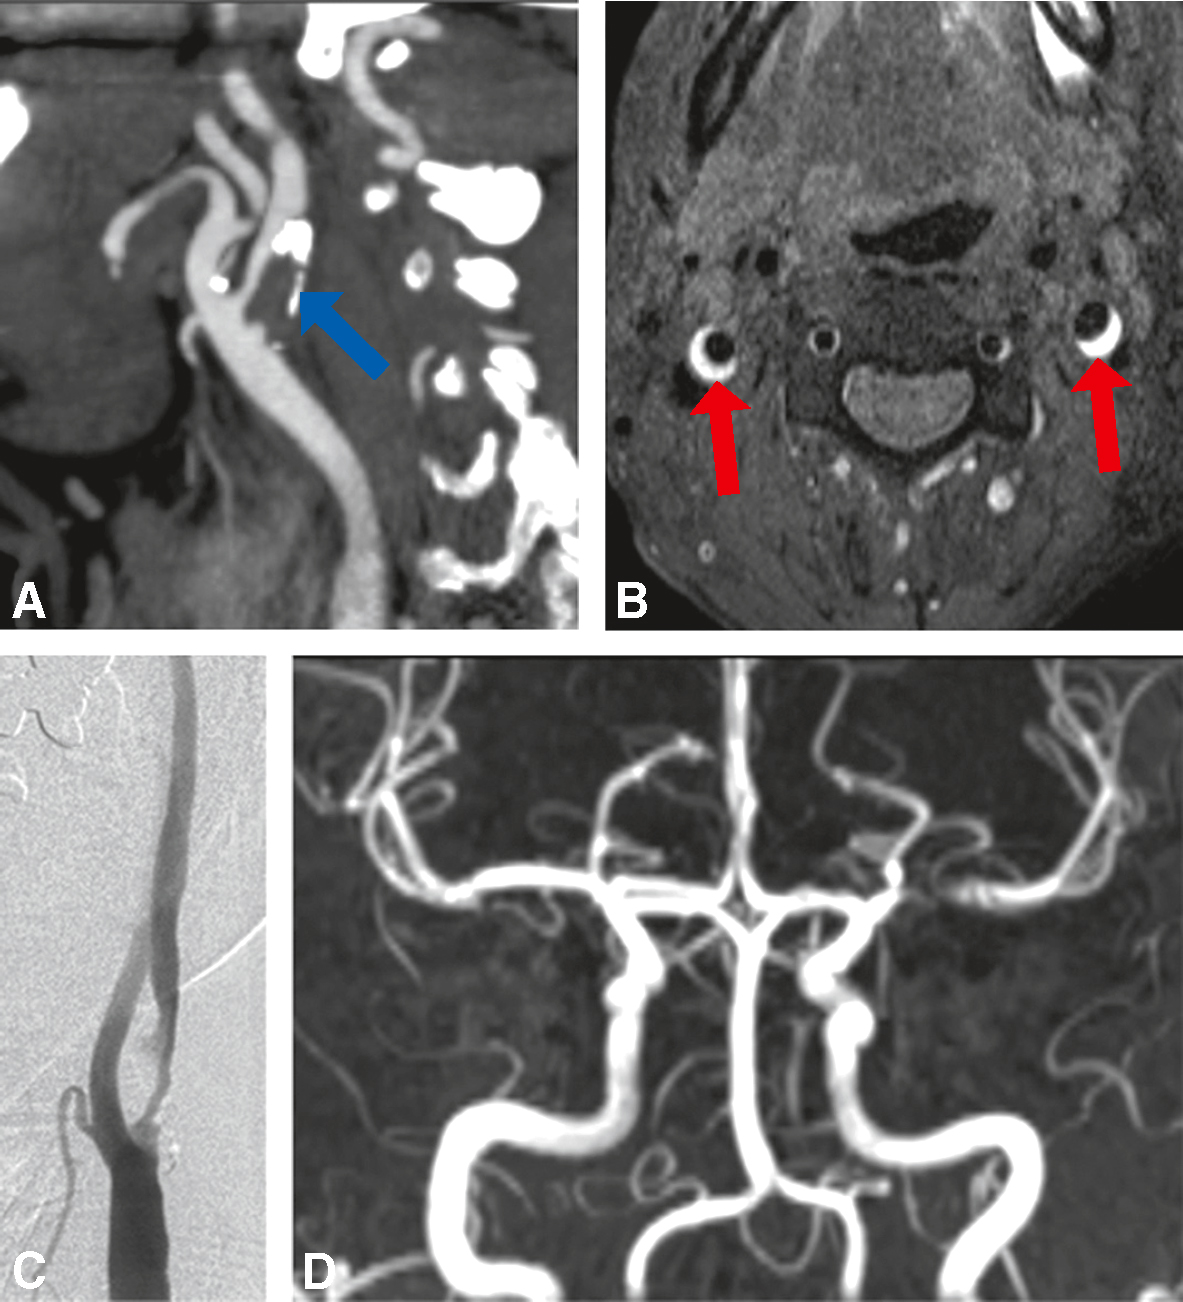

Fig. 28.9 Figure Explorations des troncs supra-aortiques.

A. Sténose carotidienne athéromateuse en angio-scanner (flèche bleue). B. Hématome pariétal de dissection carotidienne bilatérale (IRM séquence T1 SPIR – flèches rouges). C. Sténose carotidienne athéromateuse en artériographie. D. Sténose de l’artère sylvienne gauche en angio-IRM.

a Athérosclérose (fig. 28.9A, B et C)

• • Environ 30 % de l’ensemble des infarctus cérébraux.

b Dissections des artères cervico-encéphaliques (fig. 28.7B)

• FigureUne des causes les plus fréquentes des infarctus cérébraux du sujet jeune (environ 20 %).

• Figure La dissection correspond au développement d’un hématome dans la paroi de l’artère, responsable d’une sténose (avec risque d’embole distal), voire d’une occlusion de l’artère disséquée.